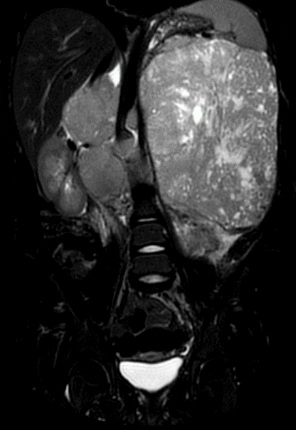

5. RMN Abdomen con contraste:

RMN: Masa retroperitoneal hipointensa en T1, realce heterogéneo con el contraste.

Hiperintensa en T2. Restringe en su mayor proporción y áreas que no restringen en relación

con áreas de necrosis.